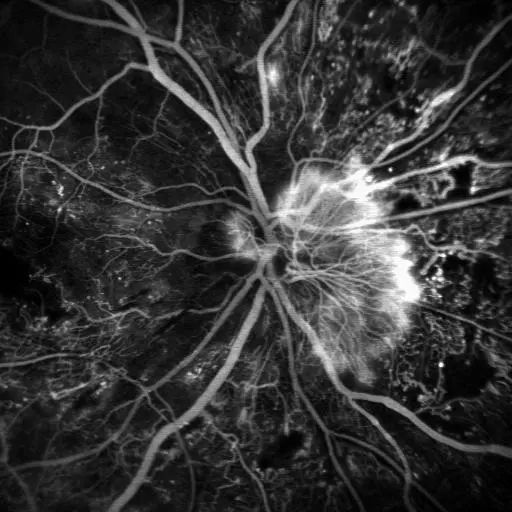

4、眼底熒光血管造影(FFA):如果發(fā)現(xiàn)患者眼底出血滲出,建議患者做熒光血管造影,了解我們?nèi)庋劭床怀鰜淼?,如是否長了新生血管,是否有很多血管都閉塞了,從而選擇治療方案;